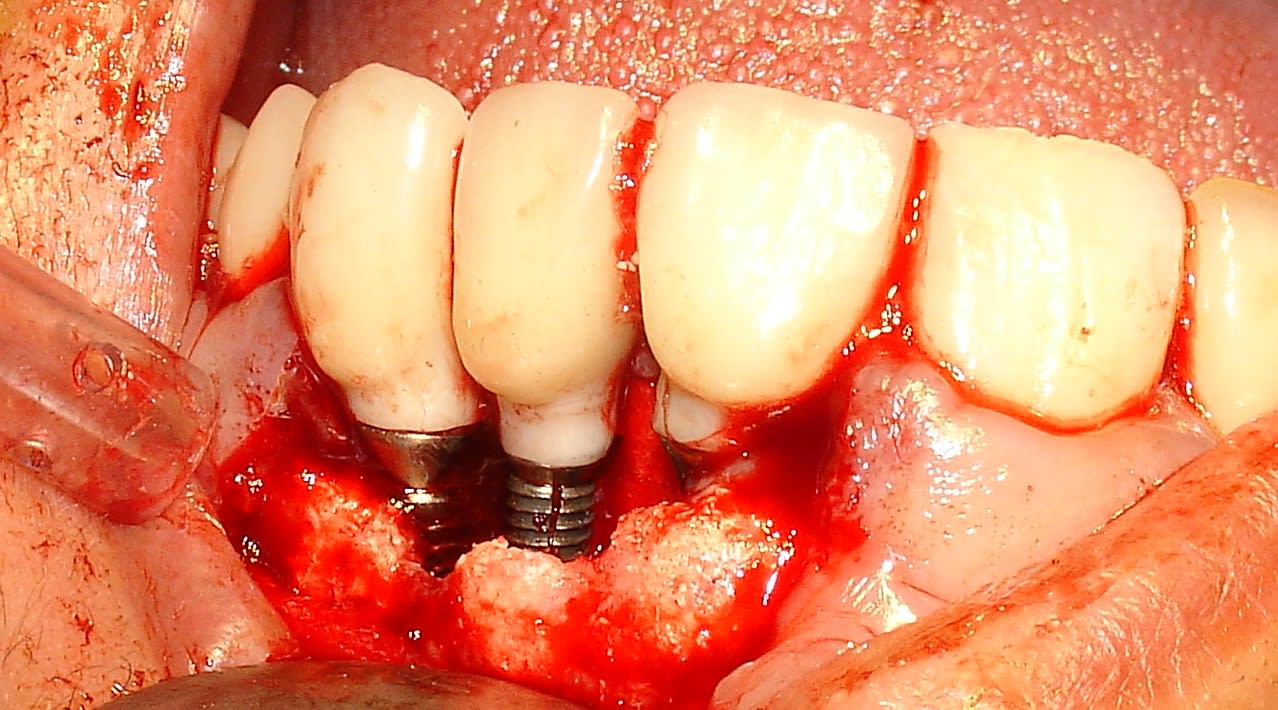

Je dirais pour le prix plus près de 300€, enfin très très cher car ils veulent se positionner en premium. Je sais j'y ai cru jusqu'à ce que les fractures arrivent.....fracture d'implant!

J'ai cru à une péri implantite quelle surprise ! Merci Megagen.....et quand je leur en ai parlé évidemment je suis le seul!....MDR Si je rajoute le SAV purée je suis largement perdant.

Voici un cas de molaire (le 1er) . Cela prouve que la taille de l'implant n'est pas la cause.

L'autre cas est une 22 (peri implantite mais NON).